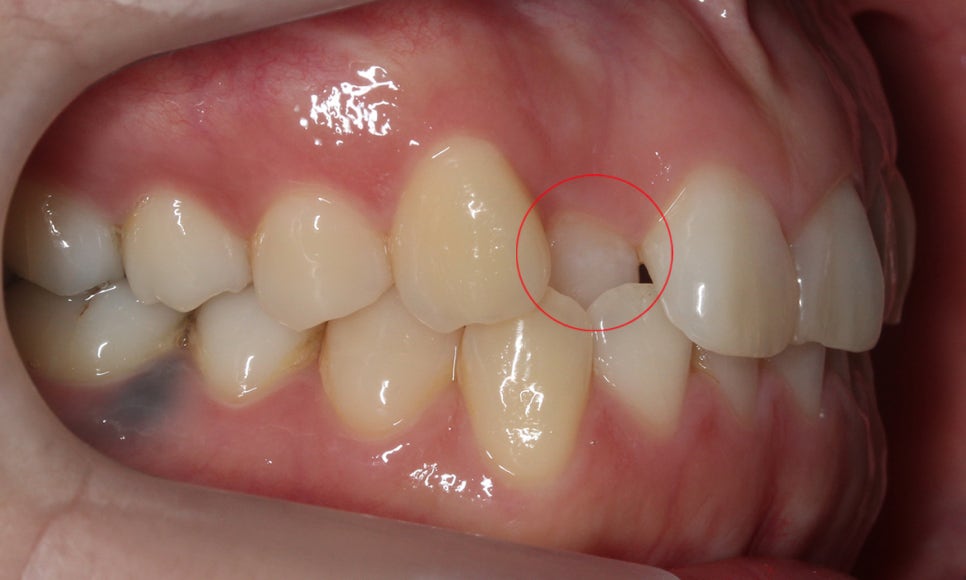

다음으로 전치부의 돌출감을 확인할 수 있는

측면 사진을 보시면 overbite 증상과

overjet 증상 정도를 알 수 있는데요,

overbite(수직피개)의 경우 상악이

하악을 얼마나 많이 덮고 있는지를 기준으로

과개교합 및 절단교합을 진단할 수 있습니다.

일반적인 경우 overbite는 약 10~20%정도가 적절하며

이보다 작으면 절단교합, 반대교합, 개방교합 등일 수 있으며

이보다 크면 과개교합 증상이 있다고 볼 수 있습니다.

overjet(수평피개)의 경우 상악과 하악 사이의 수평 거리를 뜻하며

전치부가 돌출될수록 overjet 수치가 크게 측정됩니다.

정상적인 overjet 수치는 2~3mm로 이보다 작거나 크면

문제가 있다고 볼 수 있습니다.

위의 덧니교정 Case에서는 overbite 경향이

나타나고 있는 모습으로 교합 시 상악이

과하게 물리는 것을 확인할 수 있습니다.